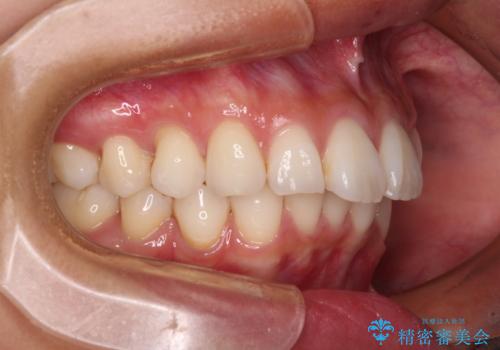

- 飛び出した前歯を気にして来院された患者様です。

口元を引っ込めるために上下左右の第一小臼歯4本を抜歯することとしました。

結婚式を行う予定があるとのことで、表側のワイヤー装置で、速やかに治療を終えられるようにしました。